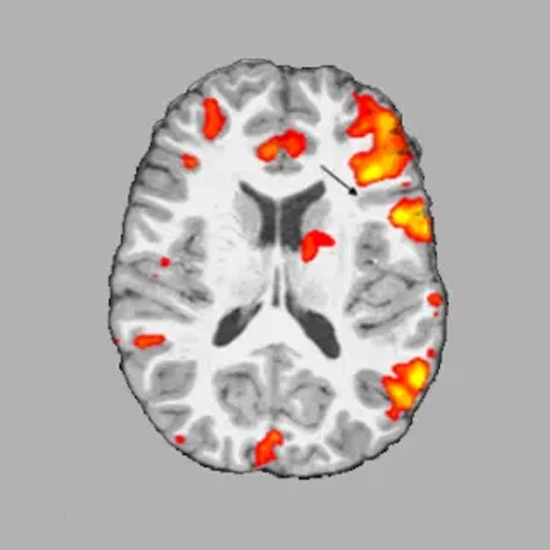

Functional MRI sanctions the detection of abnormalities of the brain, as well as the evolution of the normal functional anatomy of the brain, which cannot be adapted with other imaging techniques. Functional MRI aids assess the effects of stroke, trauma, or degenerative disease on brain function.

It examines the growth and function of brain tumors. Also teaches the planning of surgery, radiation Therapy , or other invasive treatments for the brain.